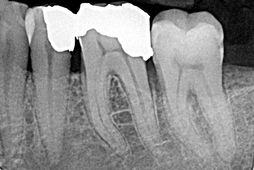

Im Inneren eines Zahnes befinden sich der Nerv und die Blutgefäße die zusammen das Zahnmark, die so genannte Pulpa, bilden. Ein Zahn hat zwischen einem und vier Wurzelkanäle. Diese werden mit Instrumenten erweitert und mit verschiedenen Spüllösungen gereinigt. Um eine langfristige Beschwerdefreiheit zu erzielen, sollte der Nervenkanal möglichst bis zur Wurzelspitze gereinigt werden. Meist wird nach der ersten Behandlung ein Medikament in den Zahn eingebracht, das verbliebene Bakterien abtötet. Um einen dauerhaften und bakteriendichten Verschluss des Wurzelkanalsystems zu gewährleisten, werden die aufbereiteten und trockenen Kanäle in einer weiteren Sitzung aufgefüllt.

- Die Längenmessung der Wurzel erfolgt zusätzlich durch ein elektronisches Messgerät.

Nach einer Wurzelkanalbehandlung sollte der Zahn über einen gewissen Zeitraum beobachtet werden. Um zu verhindern, daß der durch die Wurzelkanalbehandlung geschwächte Zahn zerbricht, empfehlen wir in den meisten Fällen eine anschließende Versorgung mit einer Krone.